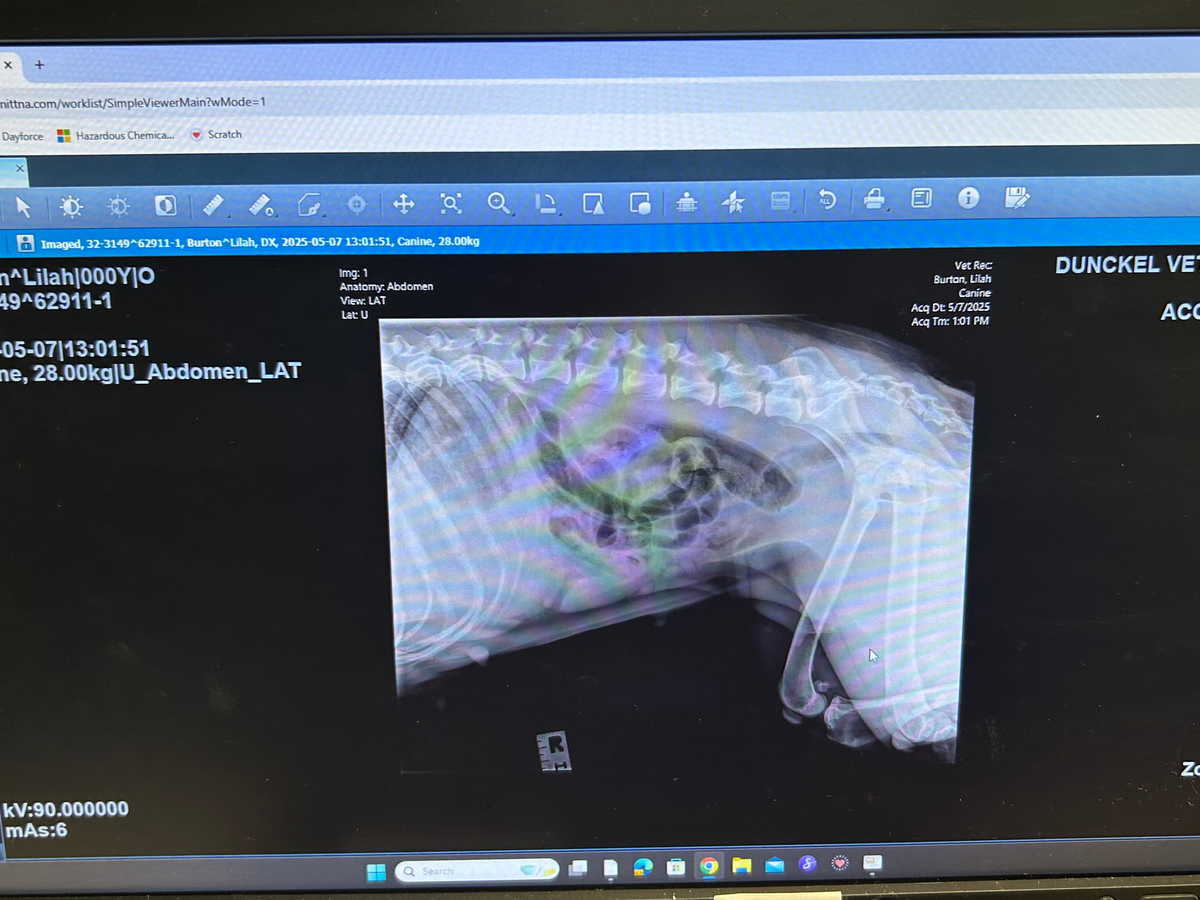

my name is Hailey Walters. I’m 21 years old and I’m struggling to pay for my dog vet bill. She has a toy stuffy, stuck in her intestine right before the colon. I need to raise 2,500. Any amount helps I spent the last on x-rays IVs, and to just be seen by the doctor. Call dunckel veterinary hospital in Davison mi. Phone number (810-653-3988) My dog Lilah Ann is my other half and I cannot go without her. Please help me save my dog’s life. God bless you share and repost.